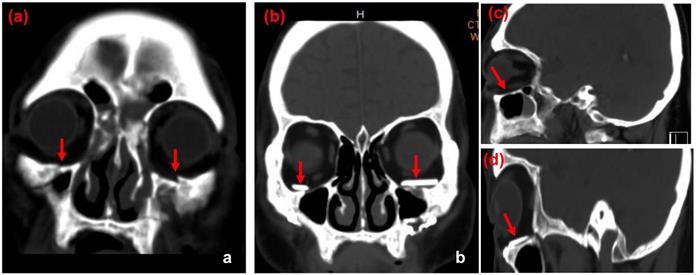

Figure 4

CT images of case 2. The comparison between preoperative CT scan of impaired orbital wall and postoperative CT scan of the orbital wall with ABCcolla® Collagen Bone graft (red arrows). (a) Pre-operative CT image with the coronal view. Fractures of bilateral inferior orbital walls can be seen (red arrows). (b) Post-operative CT image with the coronal view. ABCcolla® Collagen Bone grafts were implanted into bilateral inferior orbital walls (red arrows). (c) Post-operative CT image with the sagittal view. Fractures of bilateral inferior orbital walls are shown (red arrows). (d) Post-operative CT image with the sagittal view. ABCcolla® Collagen Bone graft was implanted into bilateral inferior orbital walls (red arrows).